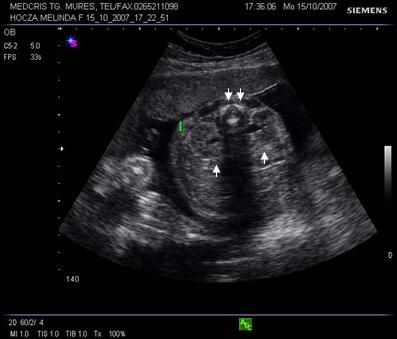

Fig. nr.176. Planul 0 de sectiune transversala ptr examinarea cordului, se incepe cu abdomenul , in care se remarca stomacul si aorta ( cu o sageata ) alaturi spre dreapta , vena cava inferioara ( cu doua sageti )